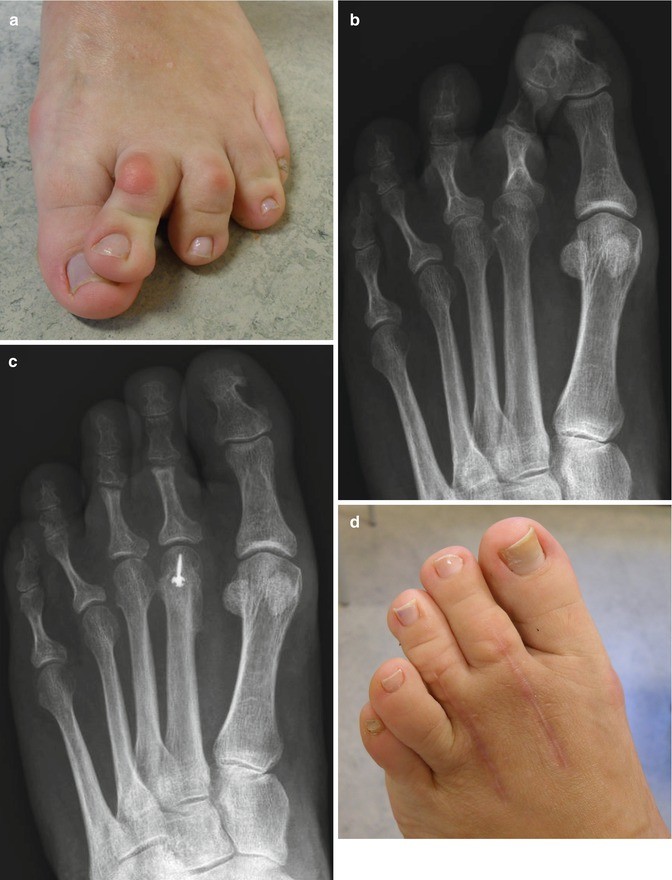

From www.foot.theclinics.com

Treatment of Flexible Lesser Toe Deformities Foot and Ankle Clinics Types Of Lesser Toe Deformities The most common types of toe deformities are hammer toe, claw toe and mallet toe. Normally, the 3 bones in the toe should form a straight line. Claw toe is a lesser toe deformity characterized by mtp hyperextension and resulting pip and dip flexion. What are common deformities of the lesser toes? The deformities on the next page. They share. Types Of Lesser Toe Deformities.